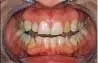

1

Worn dentition needs full-mouth reconstruction to add length to the teeth.